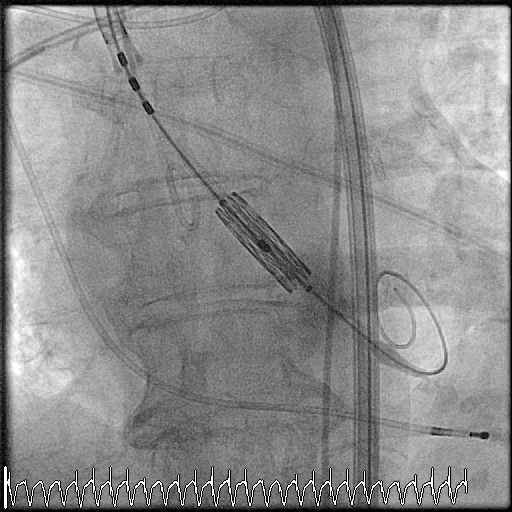

Aortovalvulopastie

Bei geeigneten Patienten wird ein Ballon über die Aortenklappe geführt und anschließend aufgeblasen. Der Gradient über der Klappe lässt sich akut durch die Dilatation um 30-50% senken. Das führt häufig zu einer deutlichen Verbesserung des subjektiven Befindens. Allerdings lässt sich keine langfristige Verbesserung hergestellen, so dass die Ballonvalvuloplastie als überbrückende Maßnahme vor geplanter Klappenersatzoperation bei hämodynamisch instabilen Patienten durchgeführt wird.